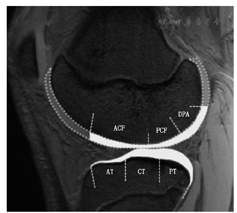

吉林大学中日联谊医院2014年6月至2015年6月招募20名参加冰雪运动的儿童及青少年与20名普通健康的儿童及青少年,分为冰雪运动组与对照组,进行3.0 T膝关节磁共振扫描,根据膝关节承重及冰雪运动的应力分布特点对膝关节股骨内侧髁、股骨外侧髁、胫骨内侧平台、胫骨外侧平台4个部位进行分区处理,对各个区域的软骨厚度、T2值进行定量测量。

冰雪运动组与对照组股骨内、外侧髁的中央前区、中央后区、后区前部以及胫骨平台内、外侧的前、中、后区的软骨厚度值差异均有统计学意义(均P<0.05,表5)。冰雪运动组与对照组股骨内、外侧髁软骨的中央前区、中央后区及胫骨平台的内侧软骨的前、中、后区软骨的T2值差异无统计学意义(P≥0.05,表5),而股骨内、外侧髁软骨的股骨后区前部、胫骨平台内、外侧软骨的后区软骨的T2值差异有统计学意义(P<0.05,表6)。